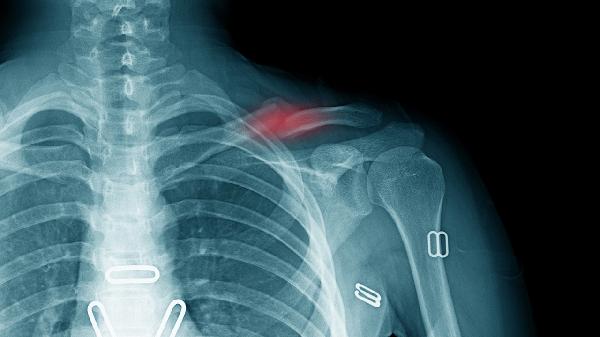

骨折的特有症状主要有畸形、异常活动、骨擦音或骨擦感、局部肿胀、功能障碍。骨折是指骨的完整性和连续性中断,通常由外伤、骨质疏松等因素引起,建议患者及时就医,完善X线、CT等检查,明确诊断后积极治疗。

骨折断端相互摩擦时可产生骨擦音,检查时可能听到或感觉到骨擦感。这种现象多见于长骨骨折,如股骨、胫骨等。骨擦音的出现通常提示骨折端有明显移位,需尽快就医处理。患者应保持患肢制动,避免移动导致骨折端进一步损伤周围血管神经。